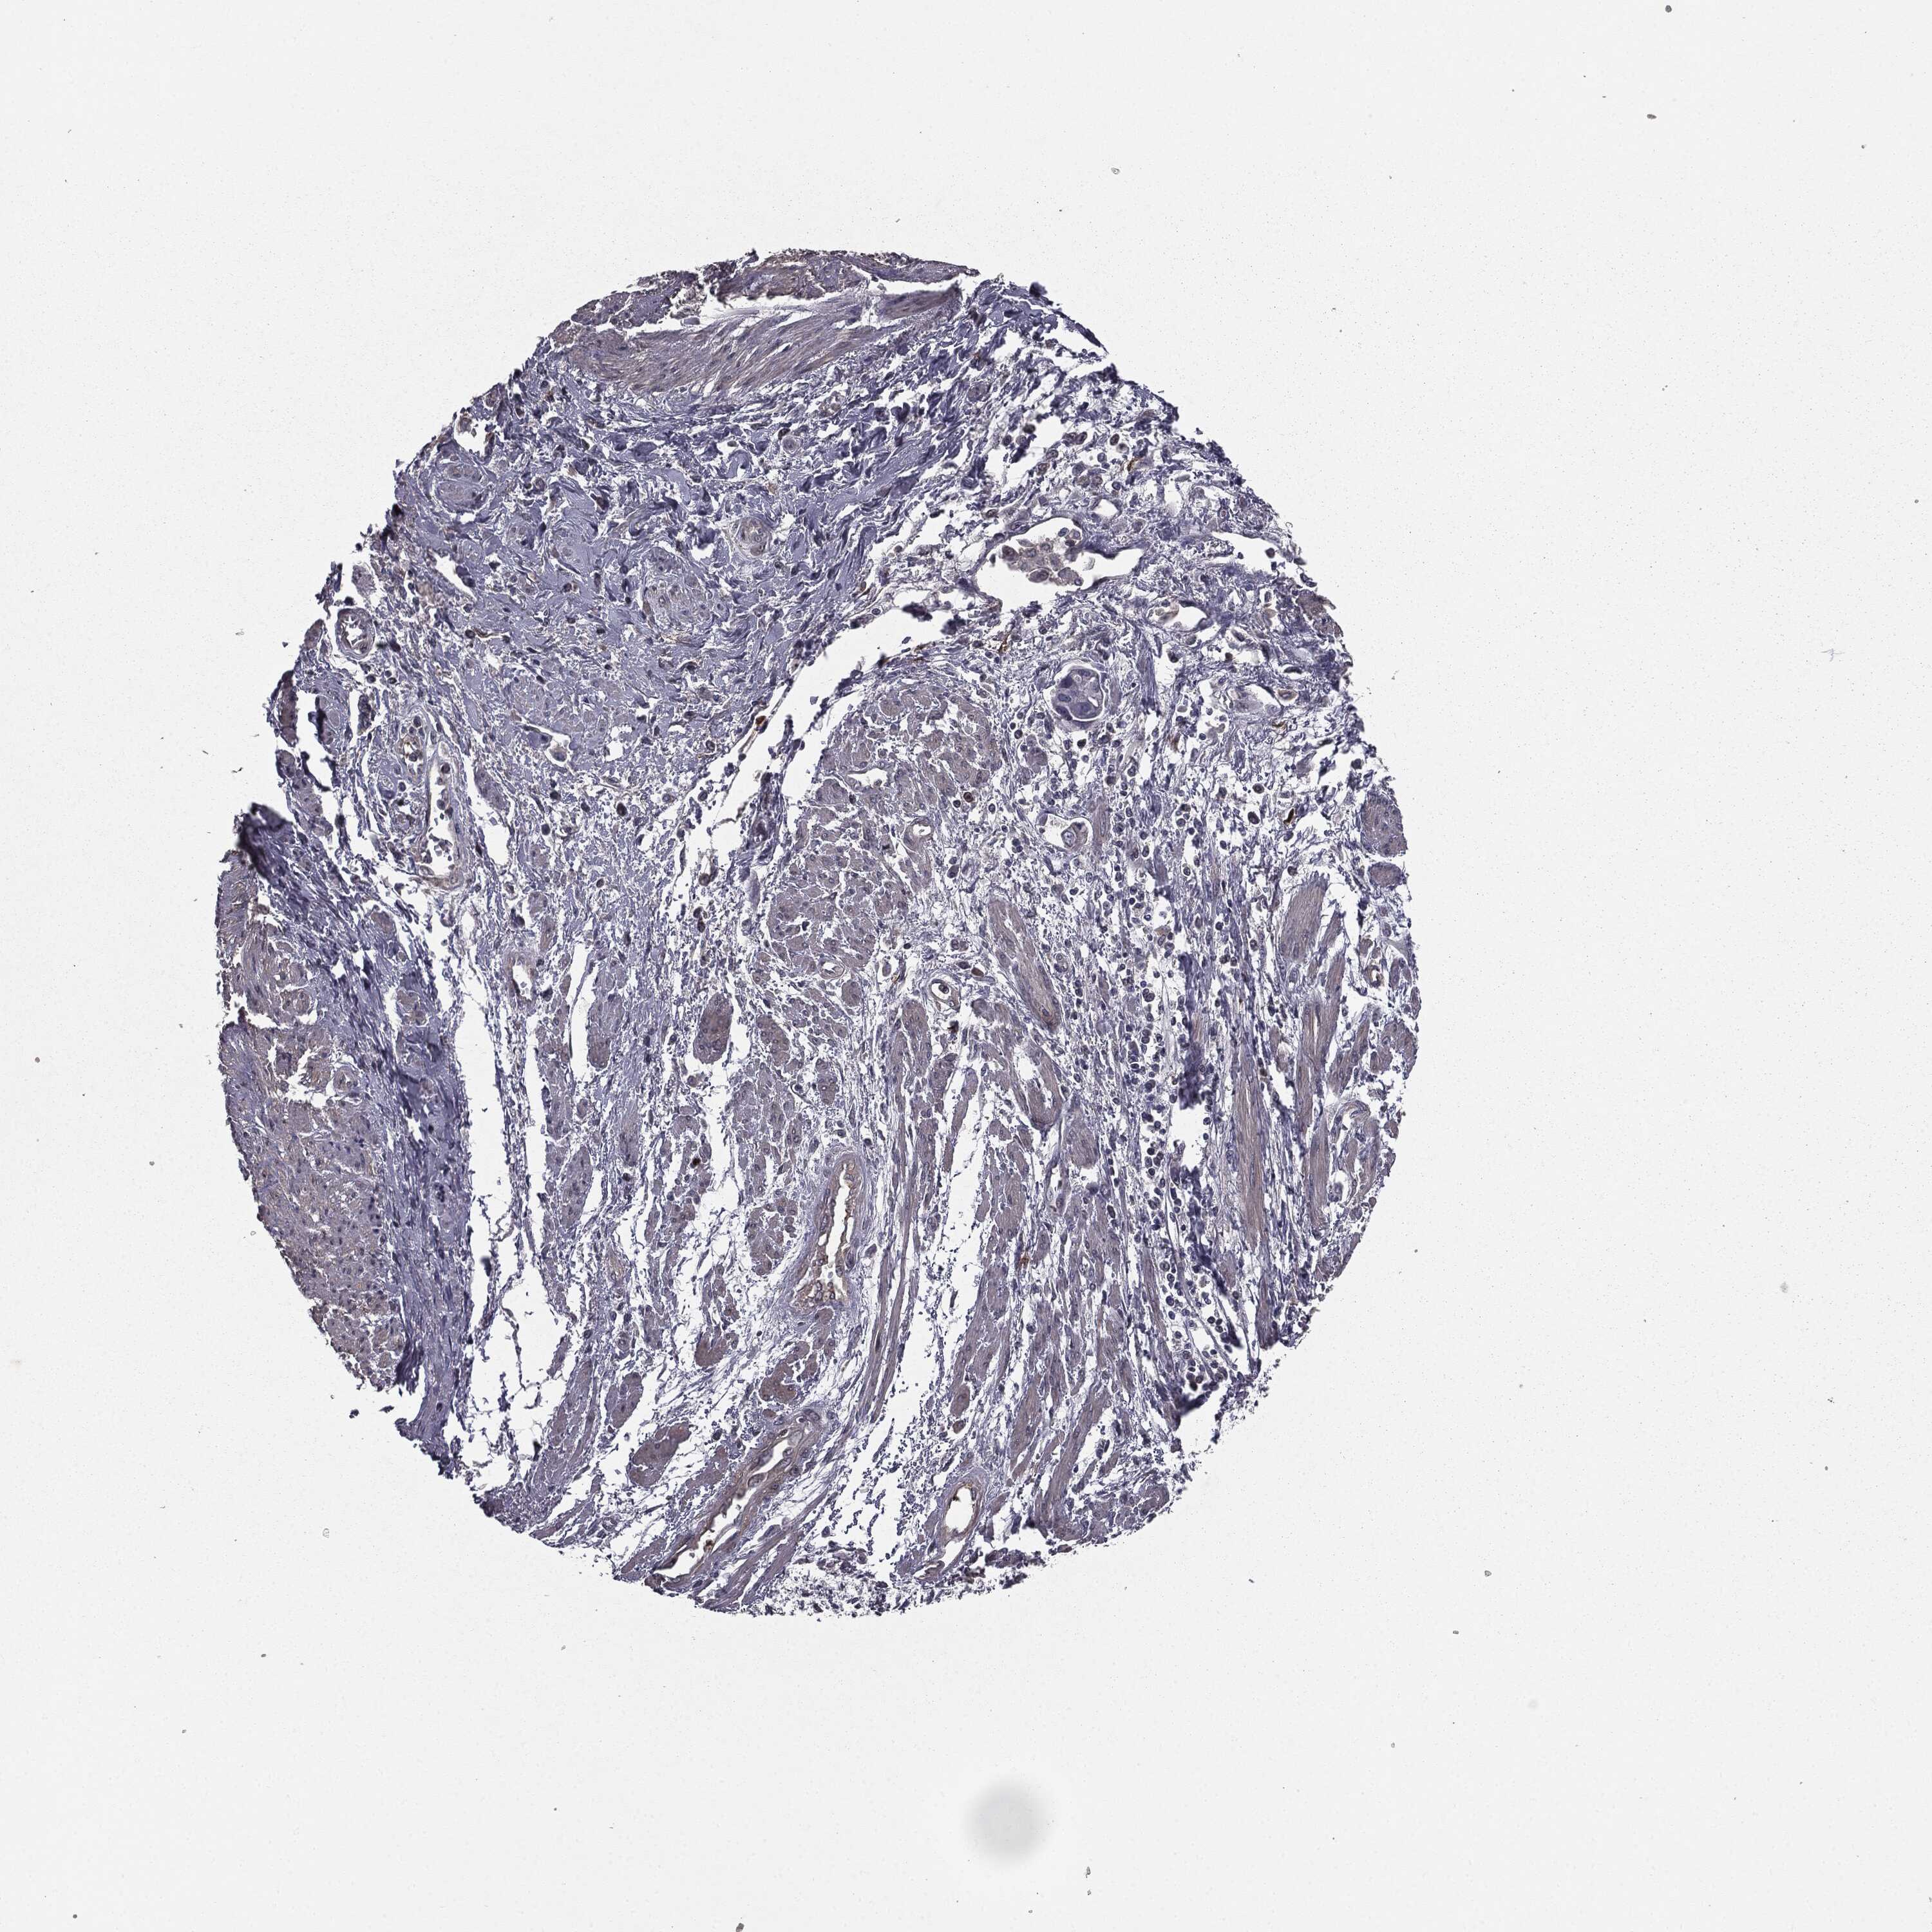

CERVICAL CANCER - Protein expressioni

A mouse-over function shows sample information and annotation data. Click on an image to view it in a full screen mode. Samples can be filtered based on level of antibody staining by selecting one or several of the following categories: high, medium, low and not detected. The assay and annotation is described here.

Note that samples used for immunohistochemistry by the Human Protein Atlas do not correspond to samples in the TCGA dataset.

Antibody stainingi

Antibody staining in the annotated cell types in the current human tissue is reported as not detected, low, medium, or high, based on conventional immunohistochemistry profiling in selected tissues. This score is based on the combination of the staining intensity and fraction of stained cells.

Each image is clickable and will lead to virtual microscopy that enables deeper exploration of all samples and also displays staining intensity scores, fraction scores and subcellular localization as well as patient and tissue information for each sample.

Antibody HPA052606

Antibody HPA077139

Staining

High

Medium

Low

Not detected

Intensity

Strong

Moderate

Weak

Negative

Quantity

>75%

75%-25%

<25%

None

Location

Nuclear

Cytoplasmic/membranous

Cytoplasmic/membranous,nuclear

Squamous cell carcinoma, NOS

Adenocarcinoma, NOS